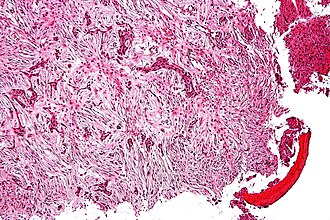

Adamantinoma. H&E stain. | |

| LM | biphasic tumour - epithelial component & fibro-osseous component |

- Biphasic tumour:[2]

- Fibro-osseous component.

- Spindle cells.

- Epithelial component.

- Classically nests of basaloid cells.